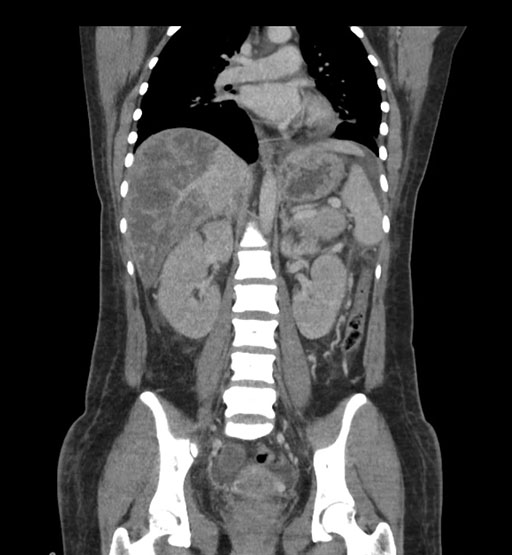

Coronal Arterial

Coronal Venous